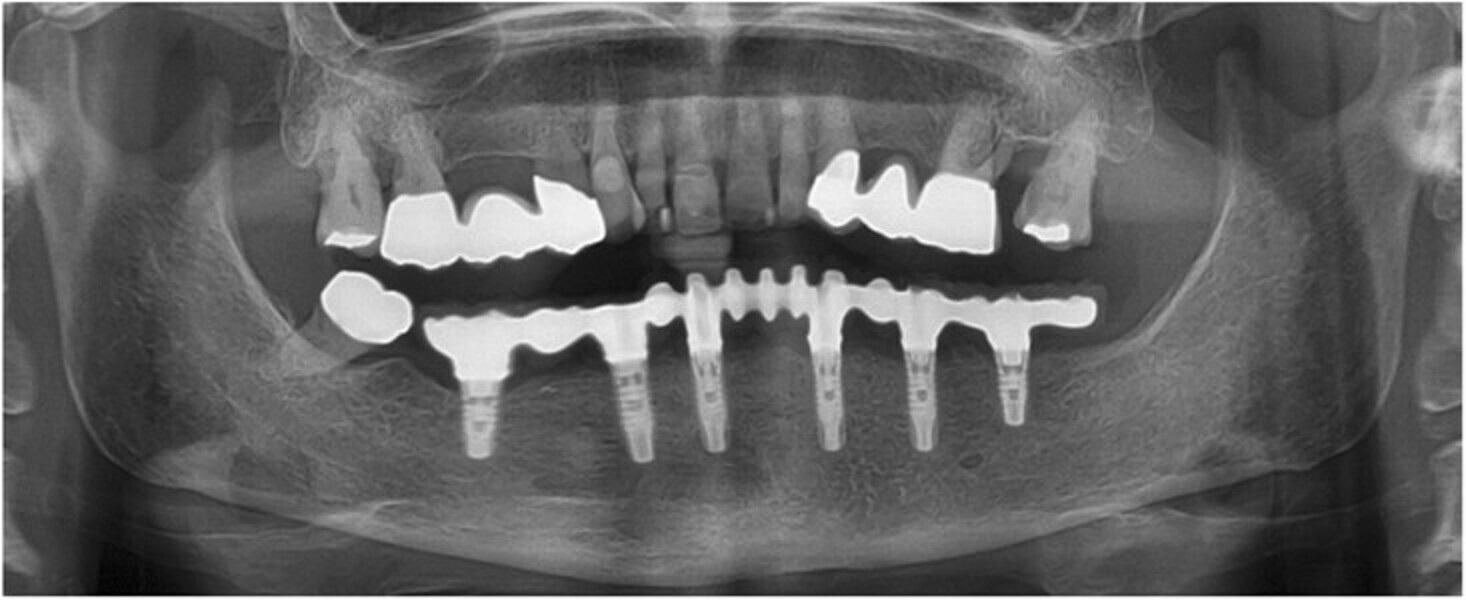

Fig. 15: Panoramic radiograph at delivery of the final CAD/CAM FDP.